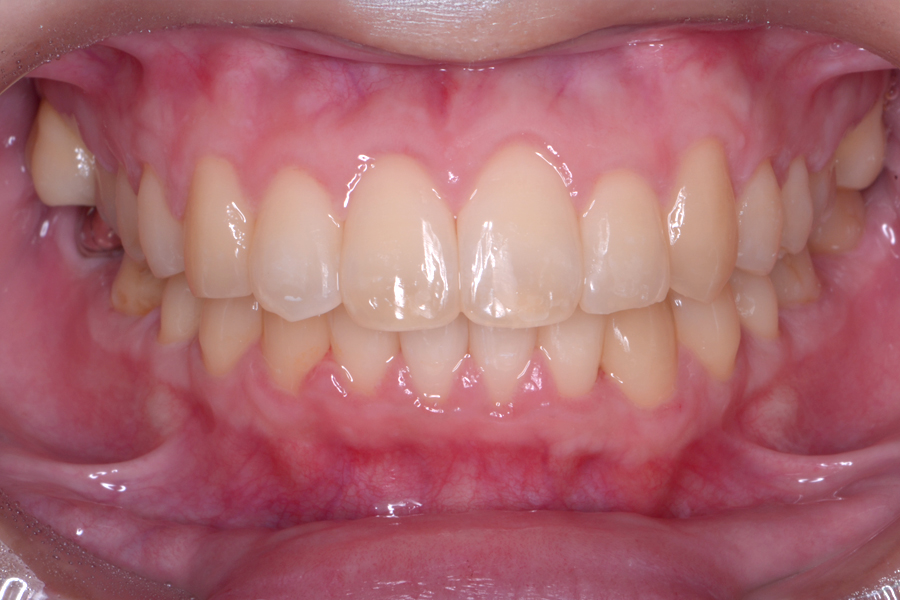

• 治療前

治療後

主訴 噛み合わせと前歯のすきっ歯を治したい

治療内容 上顎ラビアル矯正(表側矯正) リスク

リスク 後戻り